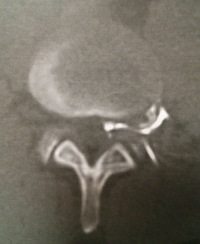

Hernie Discale

Coupe scanner